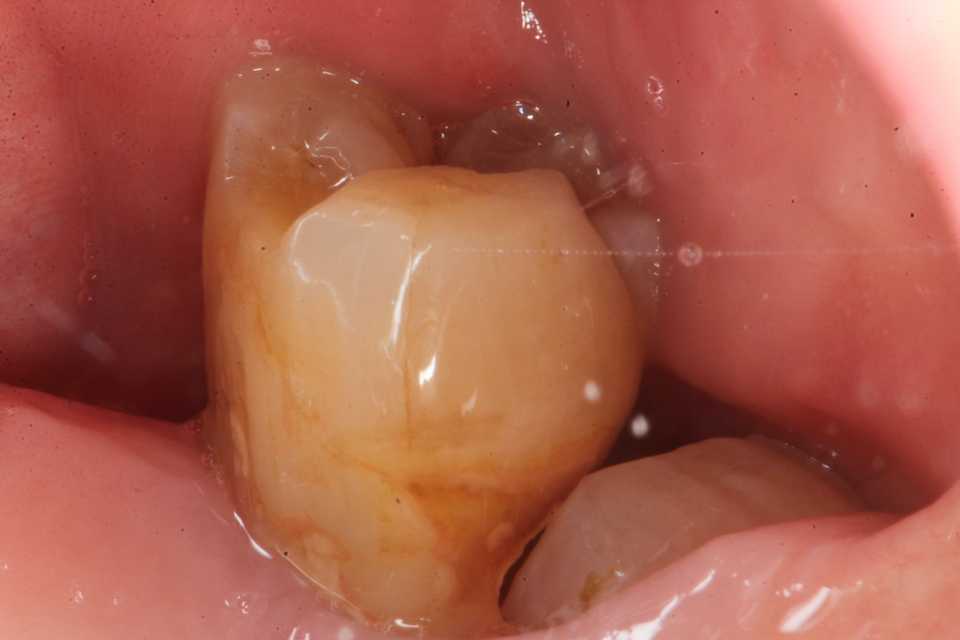

ストリップスを使わない隣接面CR(ダイレ… 2025.11.03